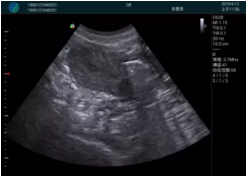

可視化甲狀腺穿刺引導(dǎo)

頸動脈血流充盈飽滿,無外溢

肝內(nèi)血管顯示清晰,血流敏感無外溢

病例二:

甲狀腺囊性結(jié)節(jié),囊壁鈣化,透聲好

甲狀腺囊性占位

2001年美國健康護(hù)理研究和質(zhì)量監(jiān)督局(AHRQ)批準(zhǔn)了一項關(guān)于提高患者安全性的報告,建議:在頸內(nèi)靜脈中心置管術(shù)時使用超聲引導(dǎo)。此后超聲引導(dǎo)穿刺被用于幾乎所有的急診穿刺操作,尤其是血管穿刺。

便攜超聲在急診穿刺中的應(yīng)用:

* 提高了穿刺成功率

* 減少了穿刺損傷及并發(fā)癥

* 縮短了操作時間

* 減輕了患者痛苦